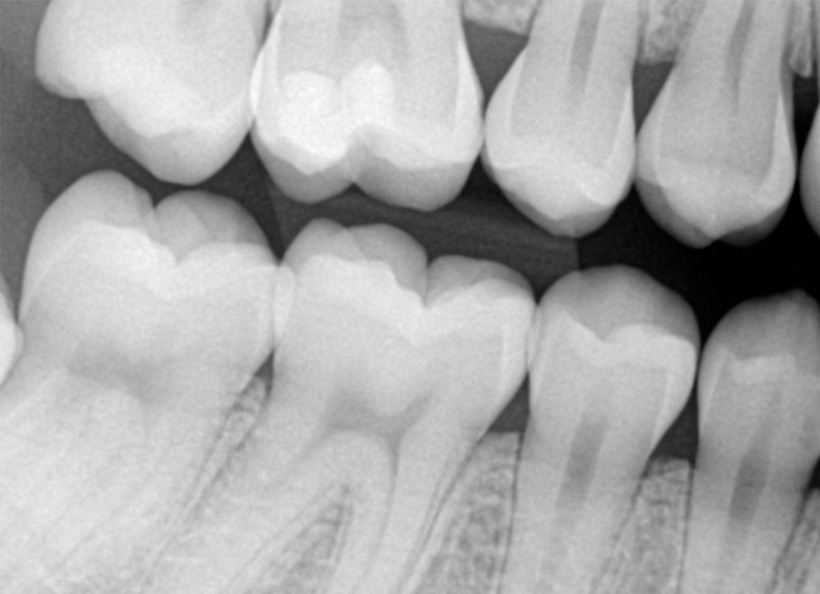

Radiografia digitală bitewing (muşcată) este o radiografie ce oferă informaţii precise (la fel ca şi radiografia retroalveolară) pe o zonă limitată a cavităţii bucale. Pe această radiografie medicul stomatolog poate vedea coroanele dinţilor, atât a dinţilor de pe maxilar, cât şi de pe mandibulă, cât şi rădăcina acestora. Este indicată în cazul cariilor interdentare, retracţiilor ososase, pungilor parodontale, etc.